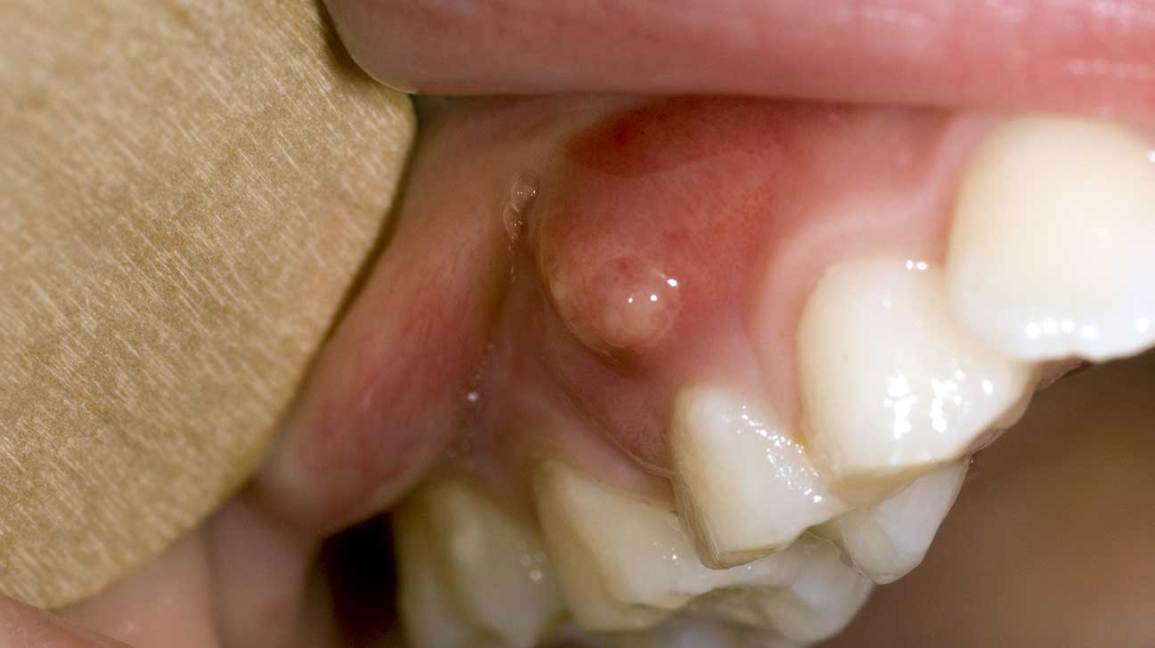

A gum boil, also known as a parulis, is a small, pus-filled bump that forms on the gums. The boil may be painful and can make it difficult to eat or drink. Gum boils are usually caused by an infection, such as bacteria or a virus. Treatment typically involves draining the pus and taking antibiotics. In some cases, surgery may be necessary to remove the gum boil.

Gum boils are a type of dental abscess. They are caused by a bacterial infection. The infection can be in the gums, the tooth, or the bone. Gum boils can be very painful. They can cause swelling in the gums, redness, and pus. The pus can drain out through the gum tissue. Gum boils can also cause fever and lymph node swelling.

When you have a gum boil, also called a parulis, it’s usually obvious. You may see a white or yellow pus-filled bump on your gums. It may be painful when you brush your teeth or eat. You might also have a fever.